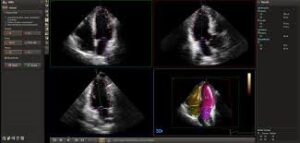

Acquisto di un nuovo ecografo Siemens che garantisce una diagnostica avanzata, integrando tecnologie all’avanguardia e applicazioni di intelligenza artificiale.

Questo nuovo ecografo, unico nel suo genere, se presente in Cardiologia pediatrica, risulta particolarmente utile per diagnosi su feti e in fase neonatale,

anche grazie alla combinazione di una qualità d’immagine superiore, intelligenza artificiale evoluta e pacchetti clinici specifici, inclusi nell’offerta.